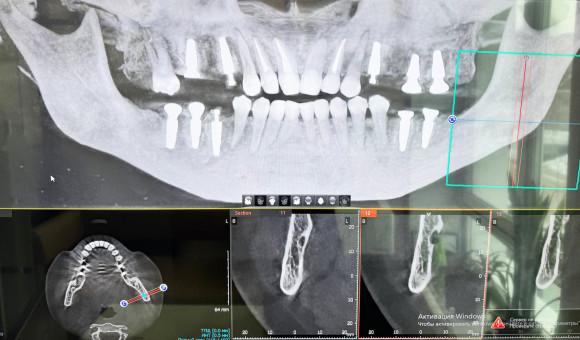

Имплантация

Имплантация зубов давно стала методом выбора восстановления  утраченных зубов. Она позволяет вернуть красоту вашей улыбки и восстановить полноценную функциональность челюстно-лицевой системы. Медицинский центр «Улыбка» в Вологде гордится своим профессиональным подходом к имплантации, используя новейшие технологии и качественные материалы.

Имплантация представляет собой процесс установки искусственных корней (имплантов) непосредственно в костную ткань челюсти. Затем на этот корень устанавливается абатмент и искусственная коронка, имитирующая натуральный зуб. Такой способ восстановления обеспечивает долговечность результата и полное восстановление функций зубов.

• Безопасность и точность процедур. Применяем современное диагностическое оборудование и компьютерное моделирование, что гарантирует точный расчет и успешную операцию.